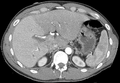

-

MDCT image. 3D image created by MDCT can clearly visualize the liver, measure the liver volume, and plan the dissection plane to facilitate the liver transplantation procedure.